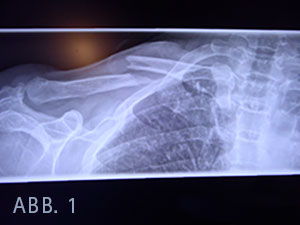

In den Röntgenaufnahmen wurde die dislozierte Fraktur in Schaftmitte nachgewiesen.

Bei Kennzeichnung der kompletten Frakturlinie zeigte sich, dass das relativ spitz zulaufende Klavikulabruchstück (Abb. 1) im Bereich der Gefäß- Nervenstraße lag, wodurch eine Arrodierung bei Sturz oder bei Schulterbewegungen vor der Ruhigstellung nicht ausgeschlossen werden kann, im Sinne eines zeitverzögerten Auftretens eines Pseudoaneurysmas der Arteria subclavia.